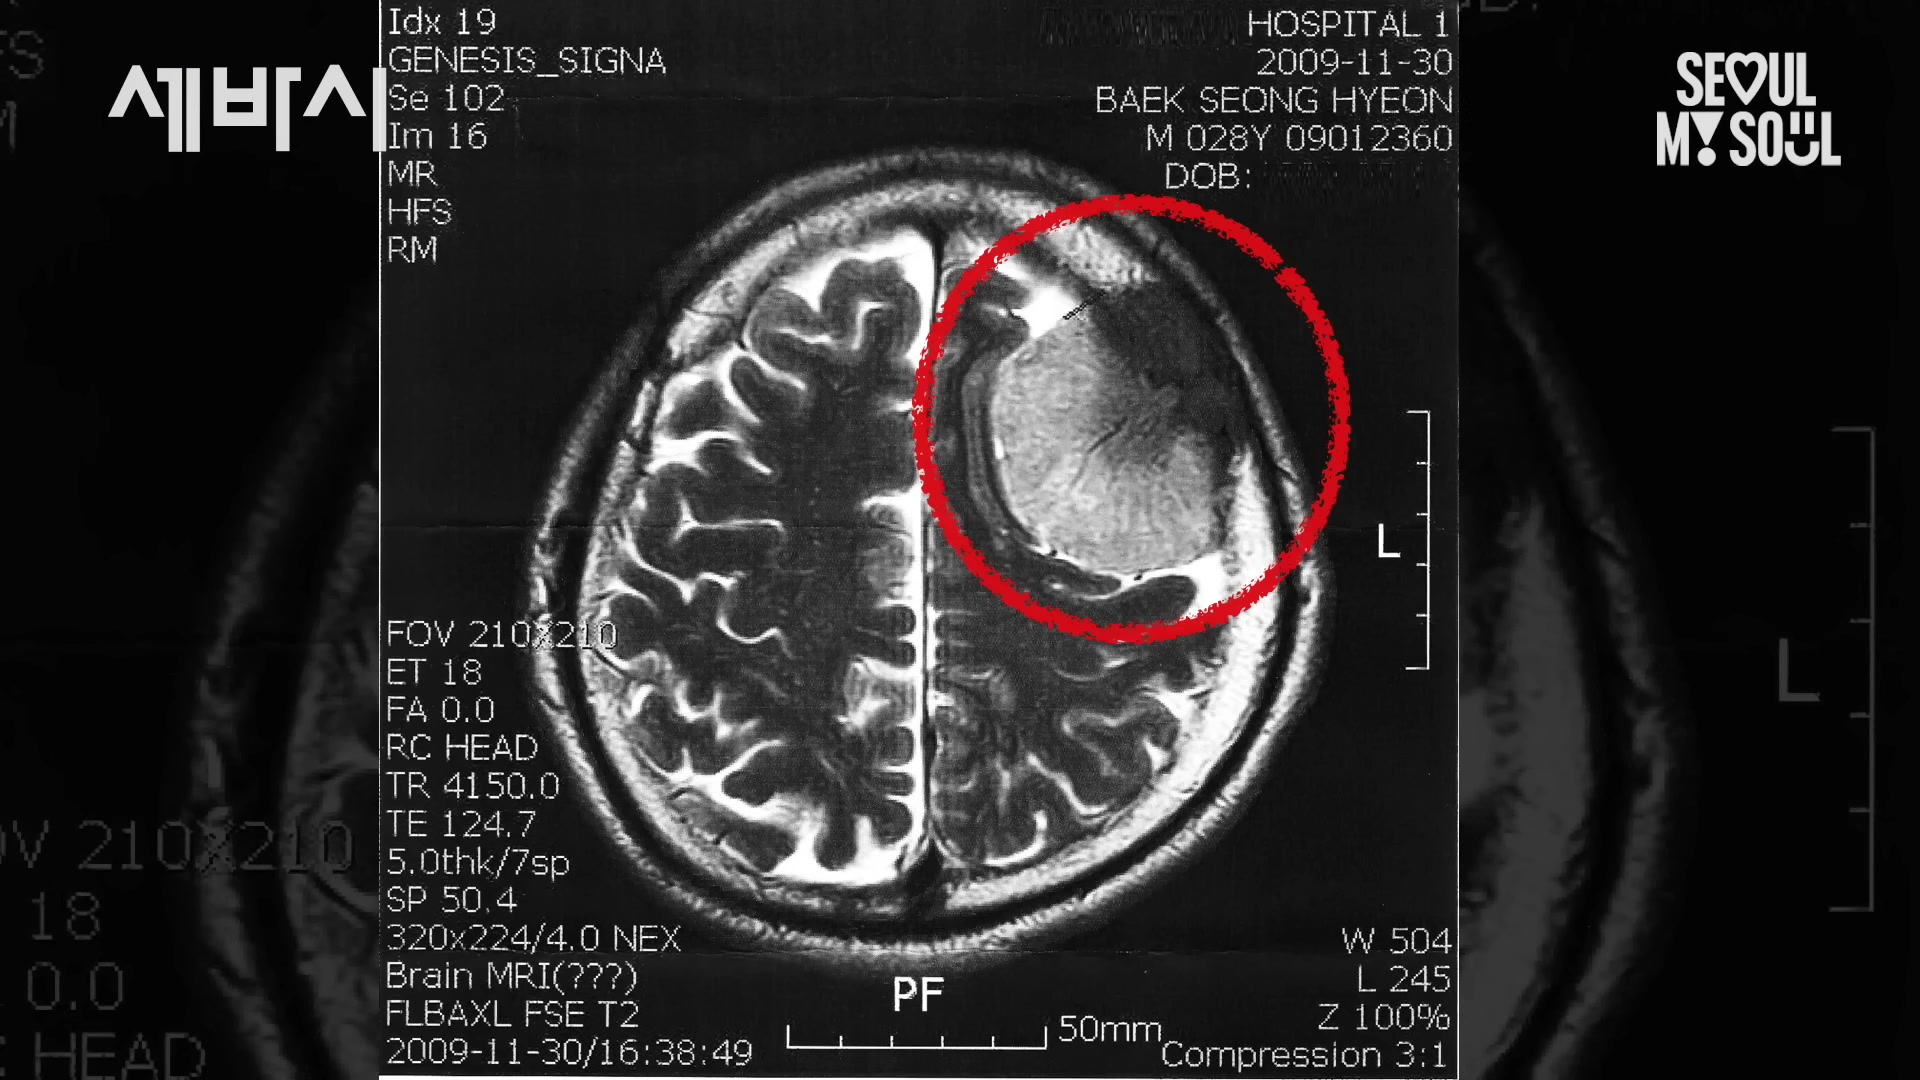

- 29세에 뇌종양 진단을 받고 생사를 오가는 수술을 겪음.

스물아홉 살에 자꾸 기절을 하는 거예요. 저는 그냥 피곤하다고 생각을 했는데 너무 쓰러지다가 교통사고가 났는데

엑스레이 찍으러 병원 갔는데 의사 선생님께서 CT를 찍어보세요.

그래서 왜요? 그랬더니 뭐가 보이는 것 같아

그 이제 너무 궁금하잖아.

그리고 이제 간호사 분께서 뭐 백성현 환자 뭐 들어오세요. 이제 의사 선생님하고 또 앞에 앉았죠.

백가씨 뇌종양입니다. 그러는 거예요.

그 제가 제가 의학적 지식이 없어서 정확히 뭔지 모르겠지만 뇌종양 뭐 심장병 백혈병 이런 건 뭔가 되게 암 그런 거 되게 큰 병 아닌가요? 그랬더니 저 사진을 보여주시는 거예요.

제 머리에 저만한 크기의 암이 있다고요. 그러는 거예요.

나는 뇌종양이야. 상상도 할 수 없었죠. 너무 건강했으니까 얼마나 무서워요.